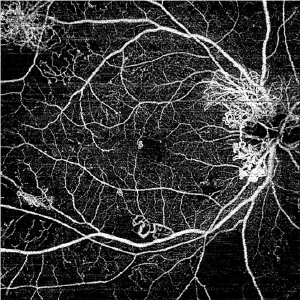

Swept Source OCT Angiography画像

精細な画像診断が可能なので網膜の微細な病変も見逃しません。